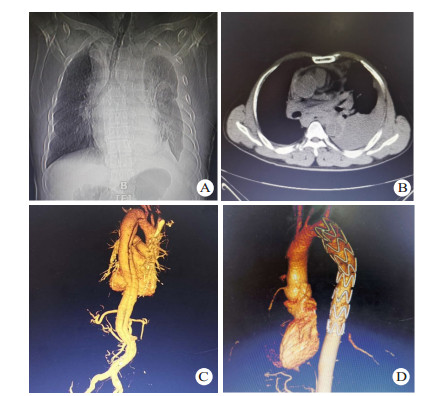

1.3 手术方法除1例主动脉夹层患者合并严重骨盆骨折及全身多处器官损伤,因失血性休克于入院后3 h死亡,其余13例患者均在全麻或局麻下行TEVAR。所有患者均在入院后48 h内完成TEVAR。TEVAR在数字减影血管造影(digital substraction antiography,DSA)室进行,转流手术及其他脏器手术在手术室进行。11例患者采用全身麻醉,2例采用局部麻醉。手术切口均腹股沟切口进行。患者取仰卧位,两侧腹股沟区充分消毒,铺无菌巾,经腹股沟切口暴露股动脉,Seldinger方法穿刺股动脉,置入5 F导管鞘,插入标记导管,将导管置于膈肌平面,注入造影剂,了解主动脉有无其他破口及腹腔重要血管分支供血情况,最后将导管尖端置于升主动脉,行正位及45°左前斜位行主动脉造影,明确主动脉破口位置及真假腔情况(图 2A),测量锚定区主动脉直径,选择合适大小的覆膜支架,进超硬导丝,取出导管及导管鞘,将支架系统输送至锚定区,定位准确后释放覆膜支架,再次造影明确夹层破口覆盖情况(图 2B),左侧锁骨下动脉供血情况,及有无内漏等。合并血胸患者行TEVAR后在介入室立即行胸腔闭式引流,并控制引流速度及引流量。伴有其他合并伤需手术的患者在进行TEVAR后转至手术室行合并伤手术; 同期脾切除、肠穿孔修补、剖胸探查止血各1例,TEVAR后2周后行骨折内固定术2例。术后所有患者均返回本重症监护室进行进一步治疗。

| 图 2 患者23岁,因高处坠落伤入院,入院后诊断TAD,破口大,急诊行TEVAR(A:术中主动脉造影显示破口位于降主动脉峡部,靠近左侧锁骨下动脉,真腔小,假腔大; B:术中再次主动脉造影,夹层破口封闭满意,无内漏) |